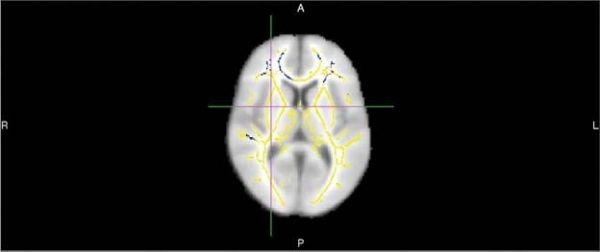

Common predictive models like standardized questionnaires used to measure cognition and tests for the APOE4 gene have limitations and—with accuracy rates of about 70-71 percent—fail to identify many people who go on to develop the disease.MRI exams of the brain using diffusion tensor imaging (DTI) are a promising option for analysis of dementia risk. DTI provides different metrics of white matter integrity, including fractional anisotropy (FA).

“With DTI you look at the movement of water molecules along white matter tracts, the telephone cables of brain,” Dr. Raji said. “When these tracts are not well connected, cognitive problems can result.”

Image: This image shows areas of reduced fractional anisotropy -- a diffusion MR imaging marker of white matter damage -- in 20 persons who develop Alzheimer's dementia compared to 20 who remain cognitively normal. These areas show up as blue-colored voxel overlaid onto a white matter skeleton (yellow colors) overlaid onto a standard template brain. (Credit: Radiological Society of North America)